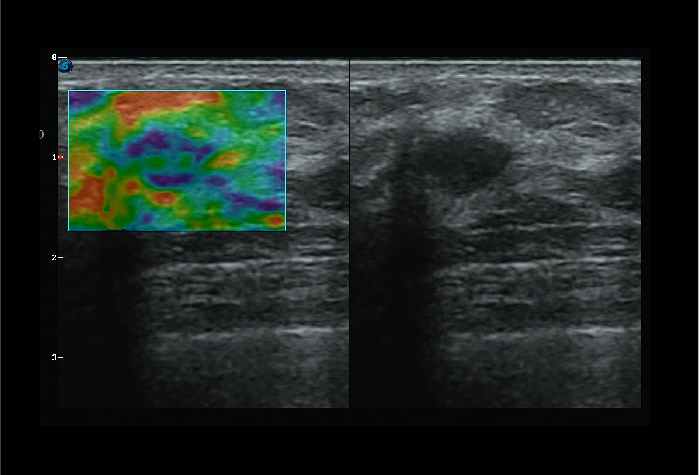

- Elsatography sử dụng được cho cả gan, thận, cho kết quả định lượng dựa trên phép đo độ đàn hồi mô

Hình ảnh thực tế trên máy siêu âm 5D SonoScape P25